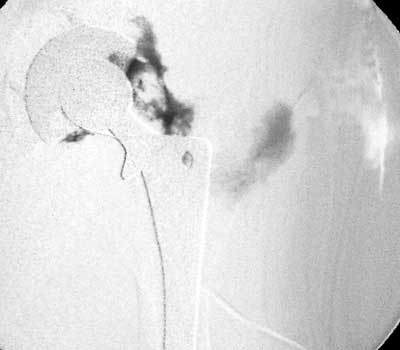

Dry tap secondary to large greater trochanteric bursa, 20

gauge spinal needle placed in bursa under fluoroscopic guidance

Scar with focal area of drainage. Dry tap secondary to large greater trochanteric bursa with

sinus tract draining to skin